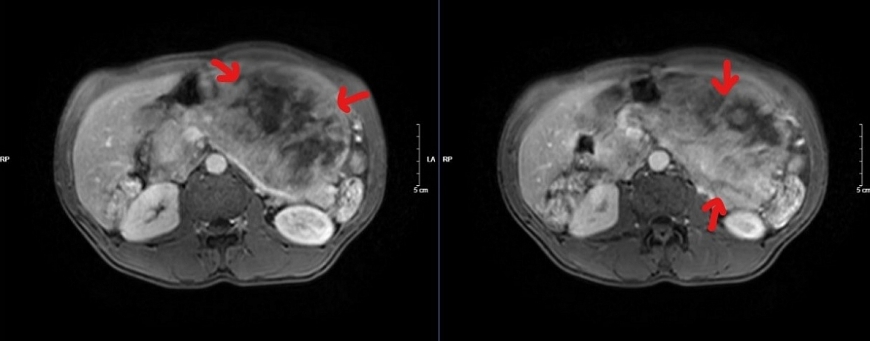

| Phim cộng hưởng từ - Hình ảnh khối lớn nửa bụng trái xâm lấn tụy |

Bệnh nhân đã phải trải qua một cuộc phẫu thuật lớn: mổ mở cắt cả khối gồm toàn bộ dạ dày, thân đuôi tụy và lách, ca mổ phức tạp, tuy diễn ra thành công ngoài mong đợi nhưng chặng đường tiếp theo với anh N sẽ nhiều khó khăn, nguy cơ bệnh dễ tái phát hoặc di căn…